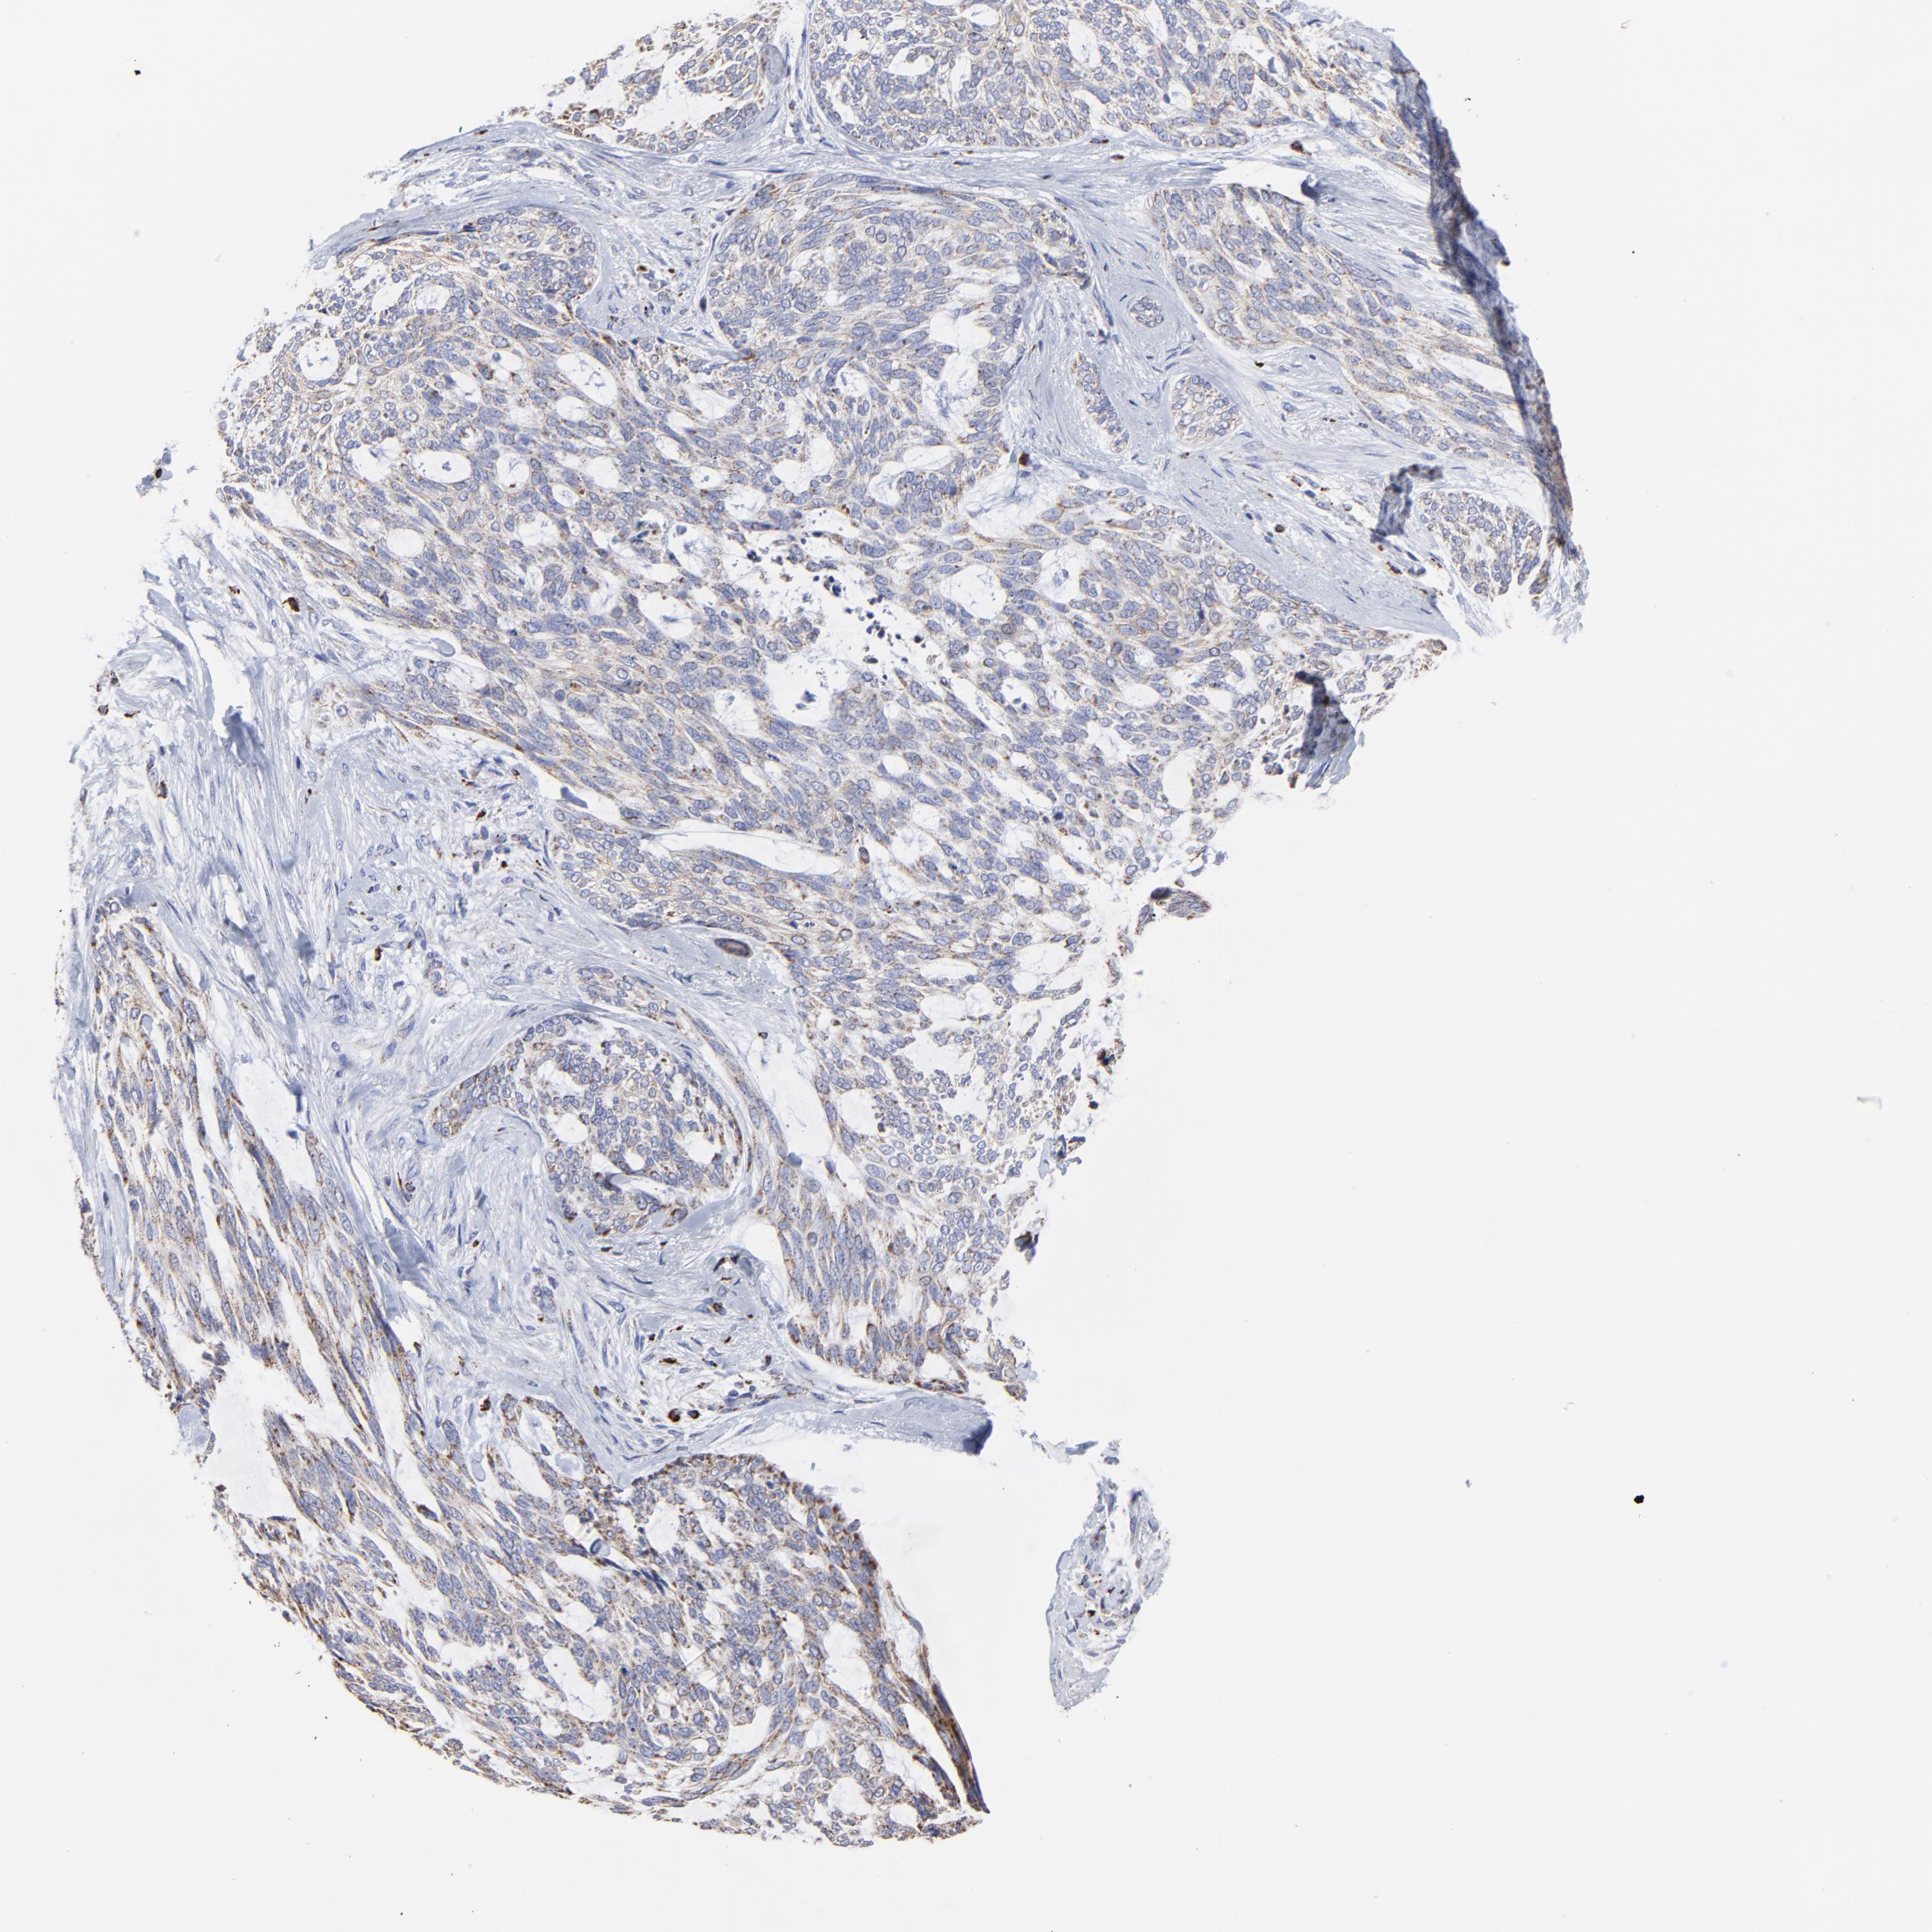

SKIN CANCER - Protein expressioni

A mouse-over function shows sample information and annotation data. Click on an image to view it in a full screen mode. Samples can be filtered based on level of antibody staining by selecting one or several of the following categories: high, medium, low and not detected. The assay and annotation is described here.

Antibody stainingi

Antibody staining in the annotated cell types in the current human tissue is reported as not detected, low, medium, or high, based on conventional immunohistochemistry profiling in selected tissues. This score is based on the combination of the staining intensity and fraction of stained cells.

Each image is clickable and will lead to virtual microscopy that enables deeper exploration of all samples and also displays staining intensity scores, fraction scores and subcellular localization as well as patient and tissue information for each sample.

Antibody HPA001931

Squamous cell carcinoma, NOS